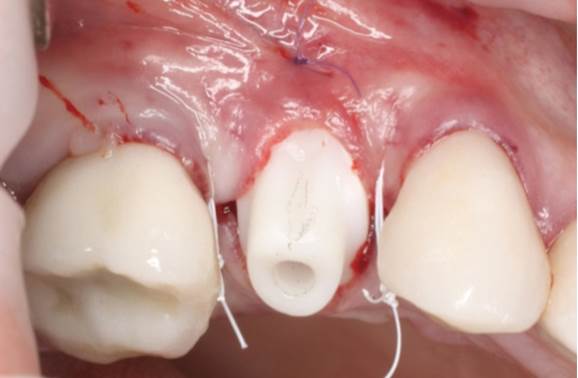

Clinical case: Extraction, immediate implant placement, & provisionalization

- Courtesy of Dr. Iulian Filipov, Romania -

Keywords

AnyRidge, R2GATE, guided surgery, immediate placement, immediate provisionalization, initial stability, Dr. Iulian Filipov, #25, maxillary posterior, immediate loading, Mega ISQ

Products:

AnyRidge implant system, R2GATE, MEGA ISQ, Digital prosthesis